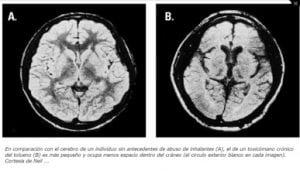

• Daño cerebral (pérdida de masa de tejido cerebral, trastornos cognitivos, trastornos de la marcha, pérdida de coordinación, pérdida de equilibrio, espasmos en las extremidades, pérdida auditiva y visual).